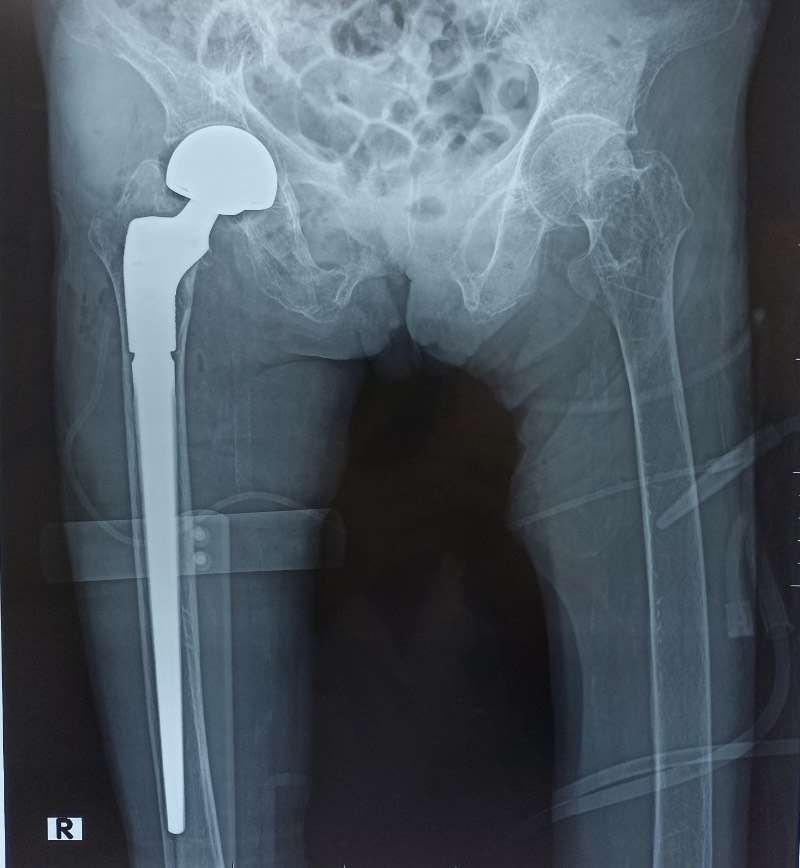

3.3. Phẫu Thuật Thay Thế Khớp (Arthroplasty)

Khi các phương pháp bảo tồn thất bại và chất lượng cuộc sống bị suy giảm nghiêm trọng do đau đớn và mất chức năng (thường gặp trong thoái hóa khớp giai đoạn cuối), phẫu thuật thay khớp (toàn bộ hoặc bán phần) là lựa chọn tối ưu. Sự tiến bộ trong vật liệu cấy ghép và kỹ thuật phẫu thuật ít xâm lấn đã cải thiện đáng kể tỷ lệ thành công và thời gian phục hồi của bệnh nhân.